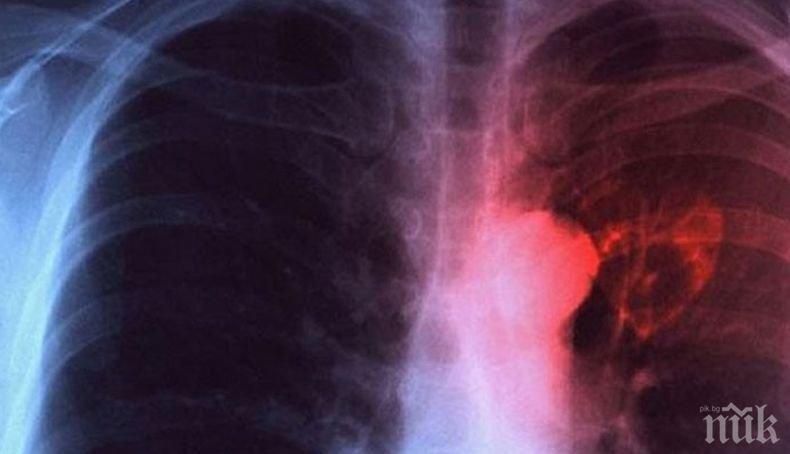

Днес е Световният ден за борба с туберкулозата. У нас през последното десетилетие се отчита трайна тенденция към намаляване на заболяемостта от туберкулоза, съобщава БНР.

Мотото на тазгодишния Световен ден за борба с туберкулозата е „Време е!” - за свят без туберкулоза! Време е за действие!" За миналата година в България са регистрирани 1 344 заболели. Запазва се тенденцията мъжете да боледуват по-често от жените. Най-засегнати са възрастовите групи от 35 до 44 години и над 65 години.

През миналата година е отчетено значително намаляване на случаите на туберкулоза при деца и младежи до 17-годишна възраст. Регистрирани са 67 случая.

Въпреки положителните тенденции в страната ни все още има области, в които заболяемостта от туберкулоза е над средната за страната. Сред тях са Кюстендил, Враца, Сливен, Ямбол, Габрово, Смолян и Перник. Важно е да знаем, че туберкулозата е лечима, стига да бъде открита навреме и да бъде проведено качествено лечение.

В България диагностиката, лечението и профилактиката на туберкулоза са безплатни, независимо от здравноосигурителния статус на гражданите.